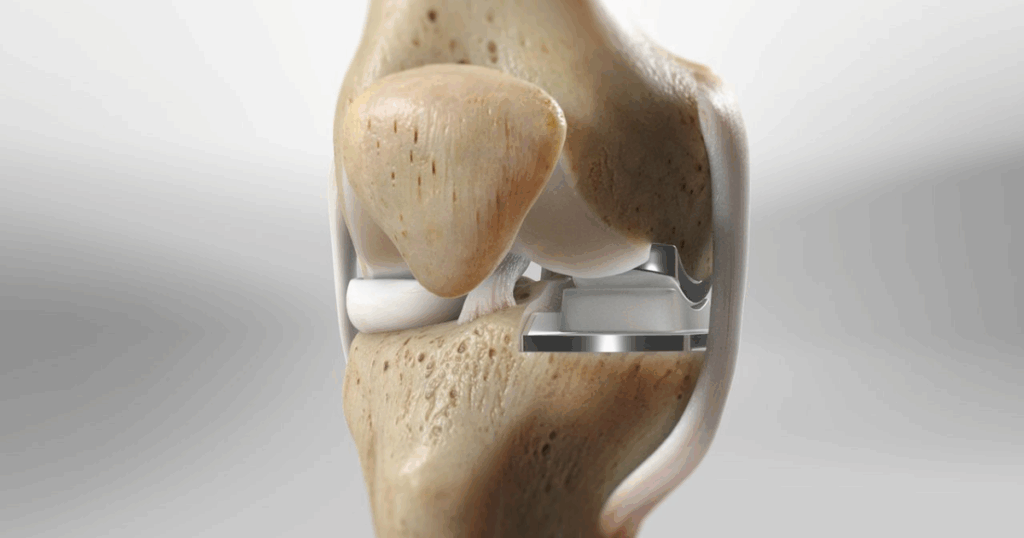

Thoái hóa khớp gối là một trong những nguyên nhân hàng đầu gây đau và hạn chế vận động ở người trung niên và cao tuổi. Khi bệnh tiến triển, lớp sụn khớp bị mòn đi, xương dưới sụn bị tổn thương, gây đau nhức và ảnh hưởng nghiêm trọng đến chất lượng cuộc sống. Trong nhiều trường hợp, tổn thương chỉ khu trú ở một khoang của khớp gối, trong khi các phần còn lại vẫn khỏe mạnh. Đối với nhóm bệnh nhân này, thay khớp gối bán phần trở thành lựa chọn tối ưu, vừa xử lý triệt để vùng khớp hư tổn, vừa bảo tồn cấu trúc lành. Đây không chỉ là giải pháp giúp giảm đau nhanh chóng mà còn duy trì cảm giác vận động tự nhiên và rút ngắn thời gian hồi phục so với thay khớp toàn phần.

Thay khớp gối toàn phần là phương pháp phẫu thuật thay thế toàn bộ bề mặt khớp gối bị tổn thương bằng vật liệu nhân tạo, nhằm loại bỏ hoàn toàn cơn đau và phục hồi khả năng vận động. Đây thường là lựa chọn cuối cùng khi các biện pháp điều trị bảo tồn không còn mang lại hiệu quả, đặc biệt ở những bệnh nhân thoái hóa khớp gối giai đoạn nặng và lan tỏa. Việc hiểu rõ quy trình phẫu thuật và tiên lượng sau mổ không chỉ giúp bệnh nhân chuẩn bị tốt về tâm lý và thể chất, mà còn đóng vai trò quan trọng trong quá trình phục hồi. Một kế hoạch điều trị được xây dựng bài bản, kết hợp giữa phẫu thuật chính xác và phục hồi chức năng đúng lộ trình, sẽ quyết định phần lớn đến hiệu quả và tuổi thọ của khớp nhân tạo.